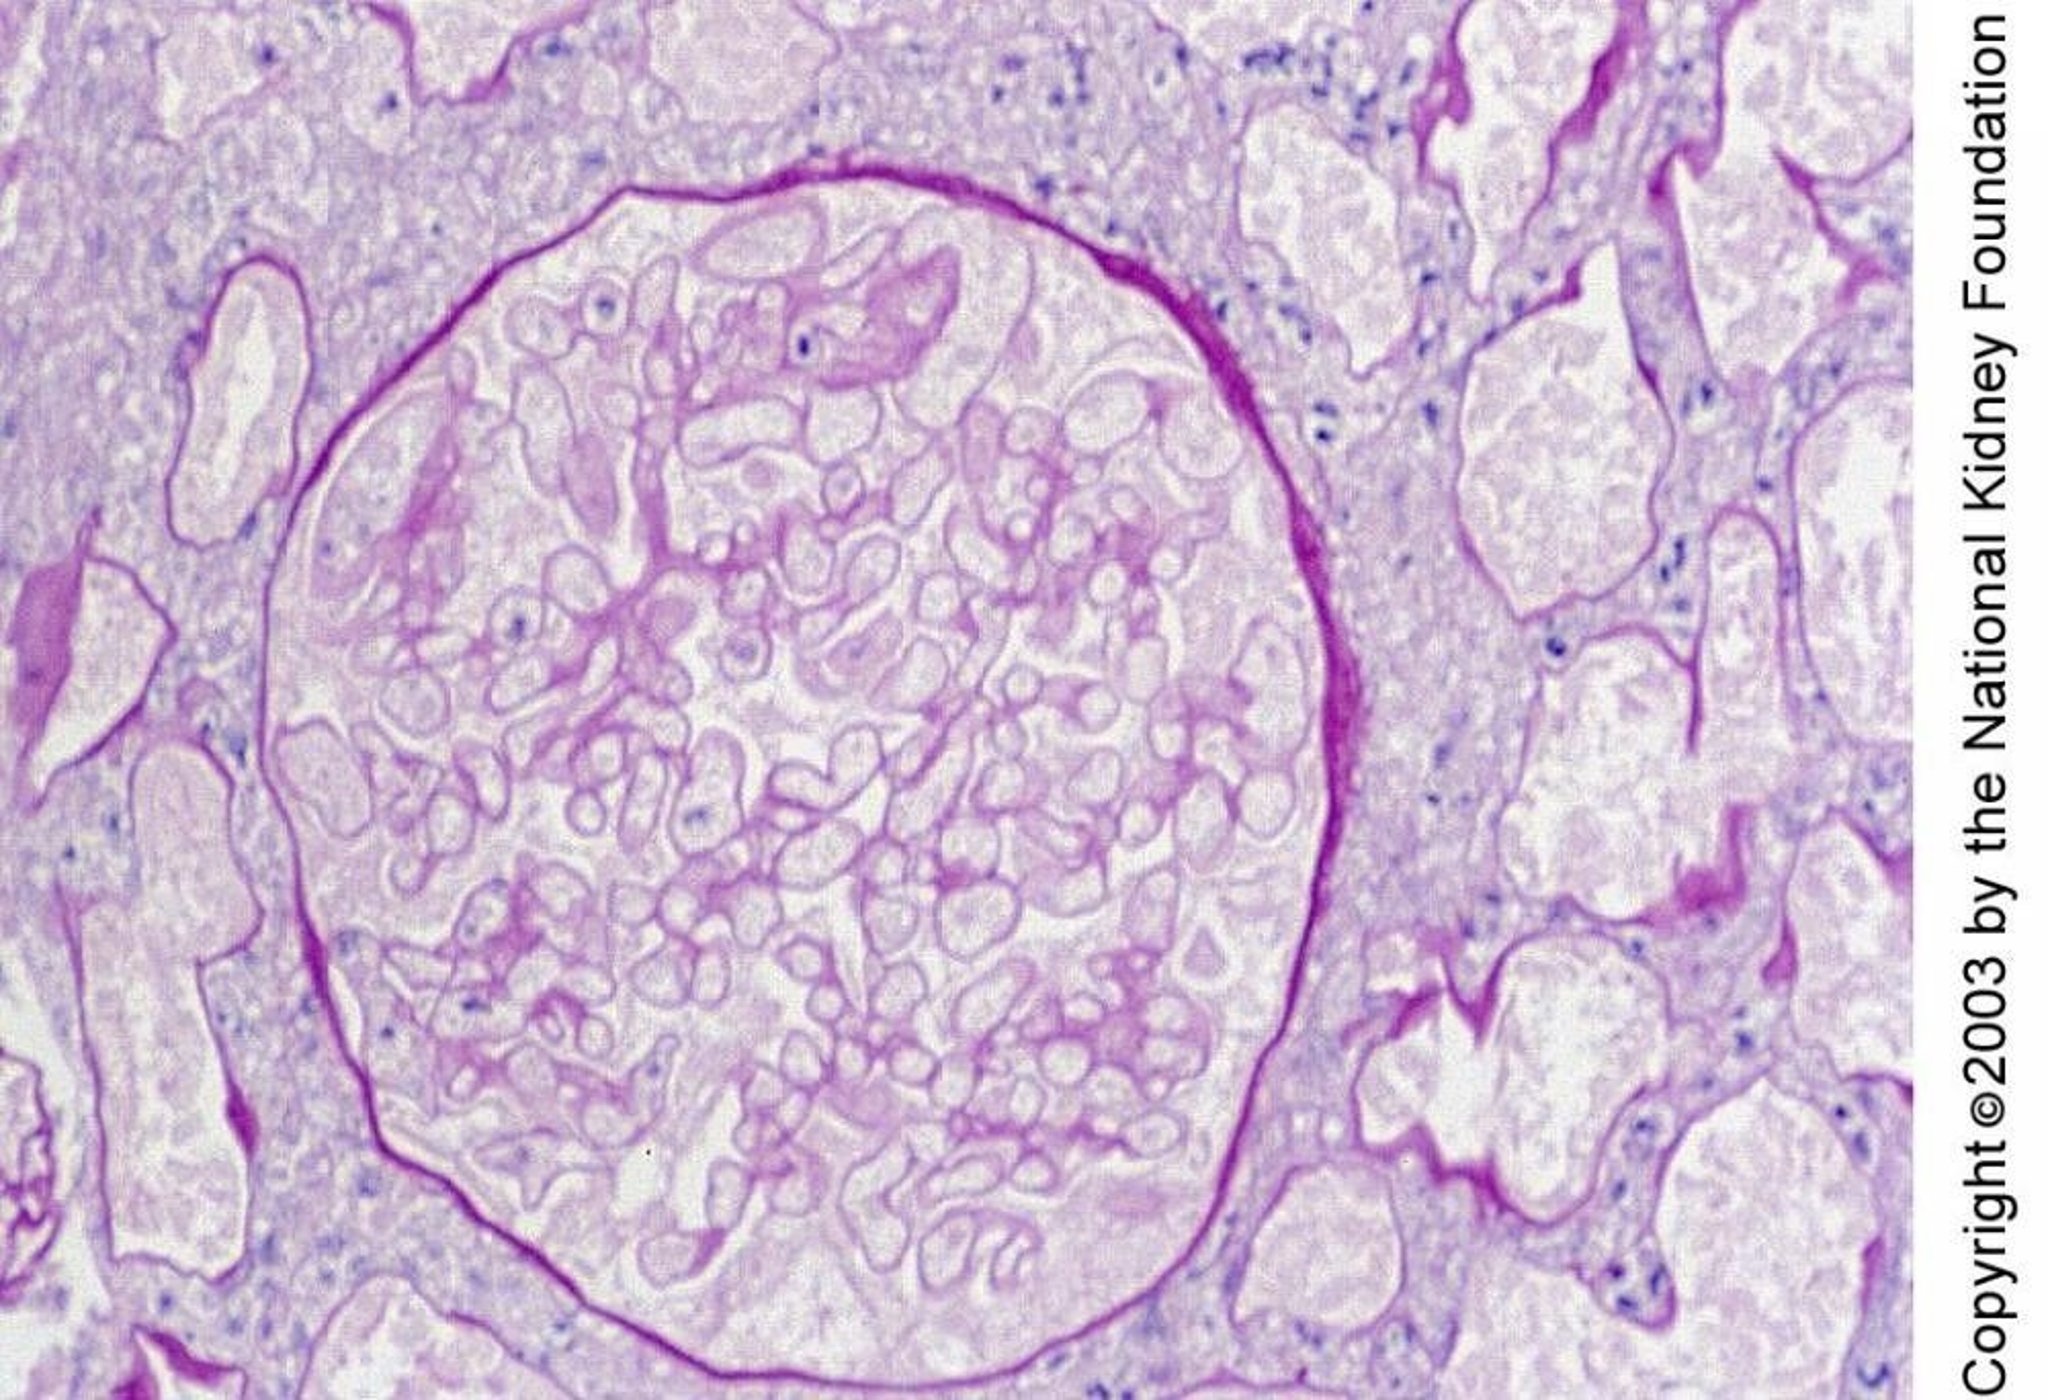

Renal Cortical Necrosis

Renal cortical necrosis is characterized histologically by necrosis of glomeruli and tubules. Necrosis in this biopsy specimen is manifest by small nuclei and ghostlike outlines of cells (periodic acid-Schiff stain, × 400).

Image provided by Agnes Fogo, MD, and the American Journal of Kidney Diseases' Atlas of Renal Pathology (see www.ajkd.org).